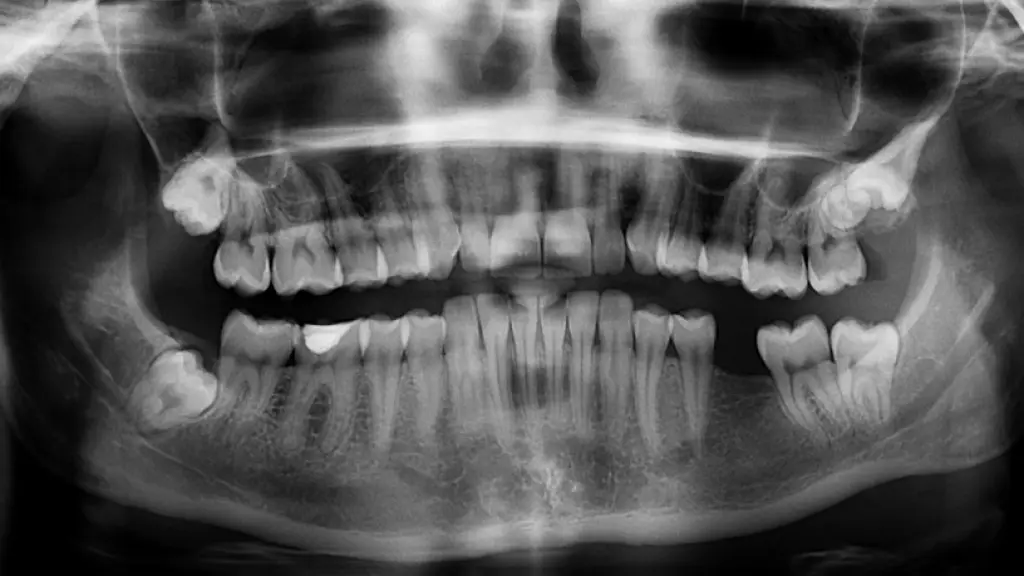

dientes, radiografía, ortopantomografía, Pixabay

dientes, radiografía, ortopantomografía / FUENTE: Pixabay